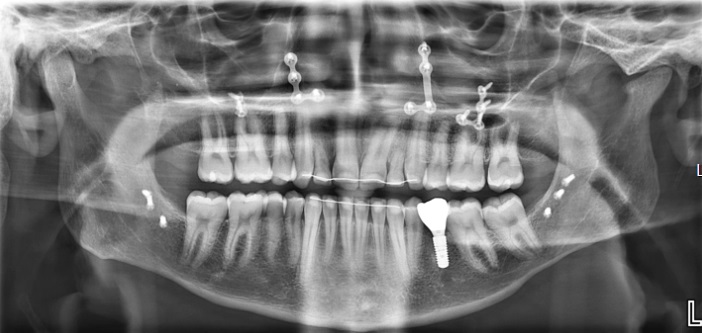

Röntgen beeld na operatie. Er is na operatie nog een implantaat geplaatst ter vervanging van een kleine kies in de onderkaak

Röntgen beeld na operatie